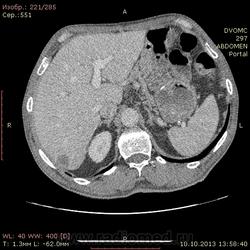

69 лет. КТ контроль от августа. Посте очередного курса химии. Начало истории здесь http://www.radiomed.ru/cases/kt-bryushnoi-polosti-adenokartsinoma-zheludka-sostoyanie-posle-rezektsii-zheludka-mts-v-pechen

Сегодня выглядит так. DICOM здесь http://files.mail.ru/2A18DCE6A6AA4546B51713D2F9C9E91A

На мой взгляд метастазов новых нет, но старые увеличились и один из пораженных л\у также увеличился.